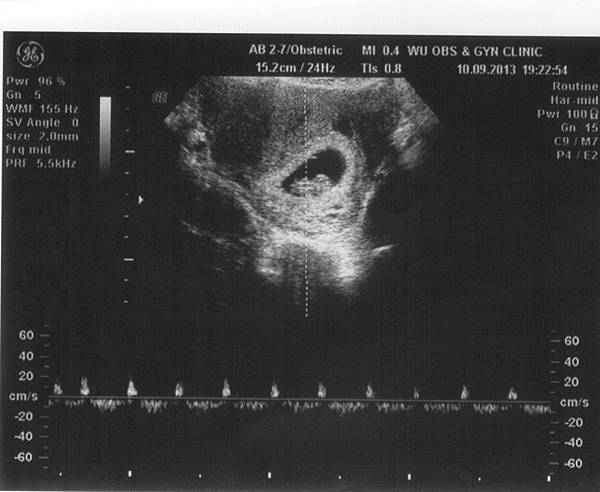

12W2D-1.jpg 12W2D-2.jpg

九月去了趟日本玩,回來就被貝拉傳染感冒,到現在都還沒好…

每天都在咳咳咳,中西醫都不敢開重藥,所以得要靠我自己本身的免疫力來打敗感冒,

回娘家休養近兩週,雖然咳嗽有好點,但咳起來還是很可怕,

我總是很害怕會影響肚子裡的小小寶貝啊~